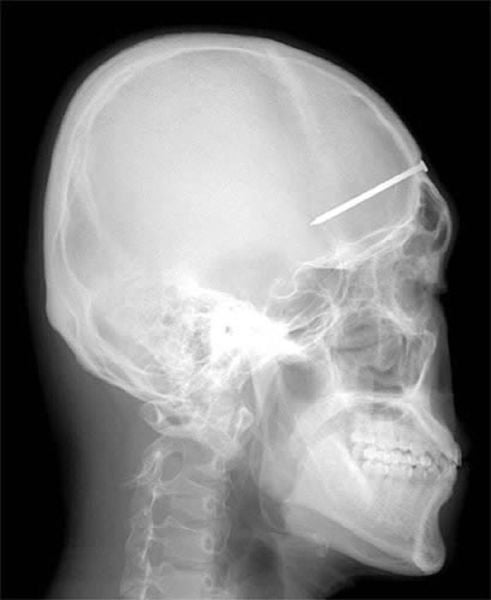

The 5-centimeter nail shown in this X-ray was found after a man came to a Seoul, South Korea, hospital complaining of a severe headache. After examining and interviewing the man, doctors speculated that the nail had been the result of an accident four years before his visit, but that the man did not know the nail was lodged in his head.